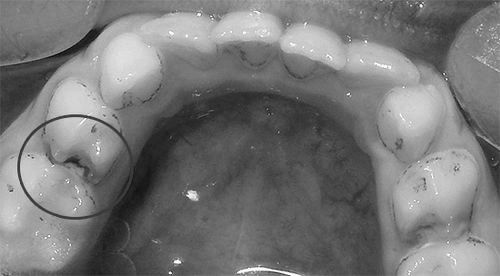

Початкова форма виглядають у вигляді білястих плям і смуг на поверхні емалі і ця поверхня стає шорсткою, втрачає природний блиск, набуваючи Меловідниє плями. Убутку тканини зуба на цьому етапі ще не відбувається.

Поверхнева форма характеризується руйнуванням зуба до емалевої межі. Залежно від індивідуальної чутливості дитини, скарги на больові відчуття можуть бути відсутні. Емаль набуває відтінок, який варіює від світло-коричневого до чорного.

Середній прийнято вважати тією формою, на яку батьки вже самостійно звертають увагу і розуміють, що настав час лікування. Тут виникають скарги на біль від подразнюючих речовин і температурних впливів, а також з'являється дірка, яка зачіпає емаль і дентин. Колір порожнини залежить від того, гостре або хронічне протягом має захворювання.

Глибоку форму рідко можна зустріти у дітей, так як він швидко переходить в пульпіт, адже камера, де розташований нерв, широка і займає велику площу в коронці зуба. Дитина часто говорить про те, що йому боляче їсти, а при прийомі їжі намагається не жувати хворий стороною.